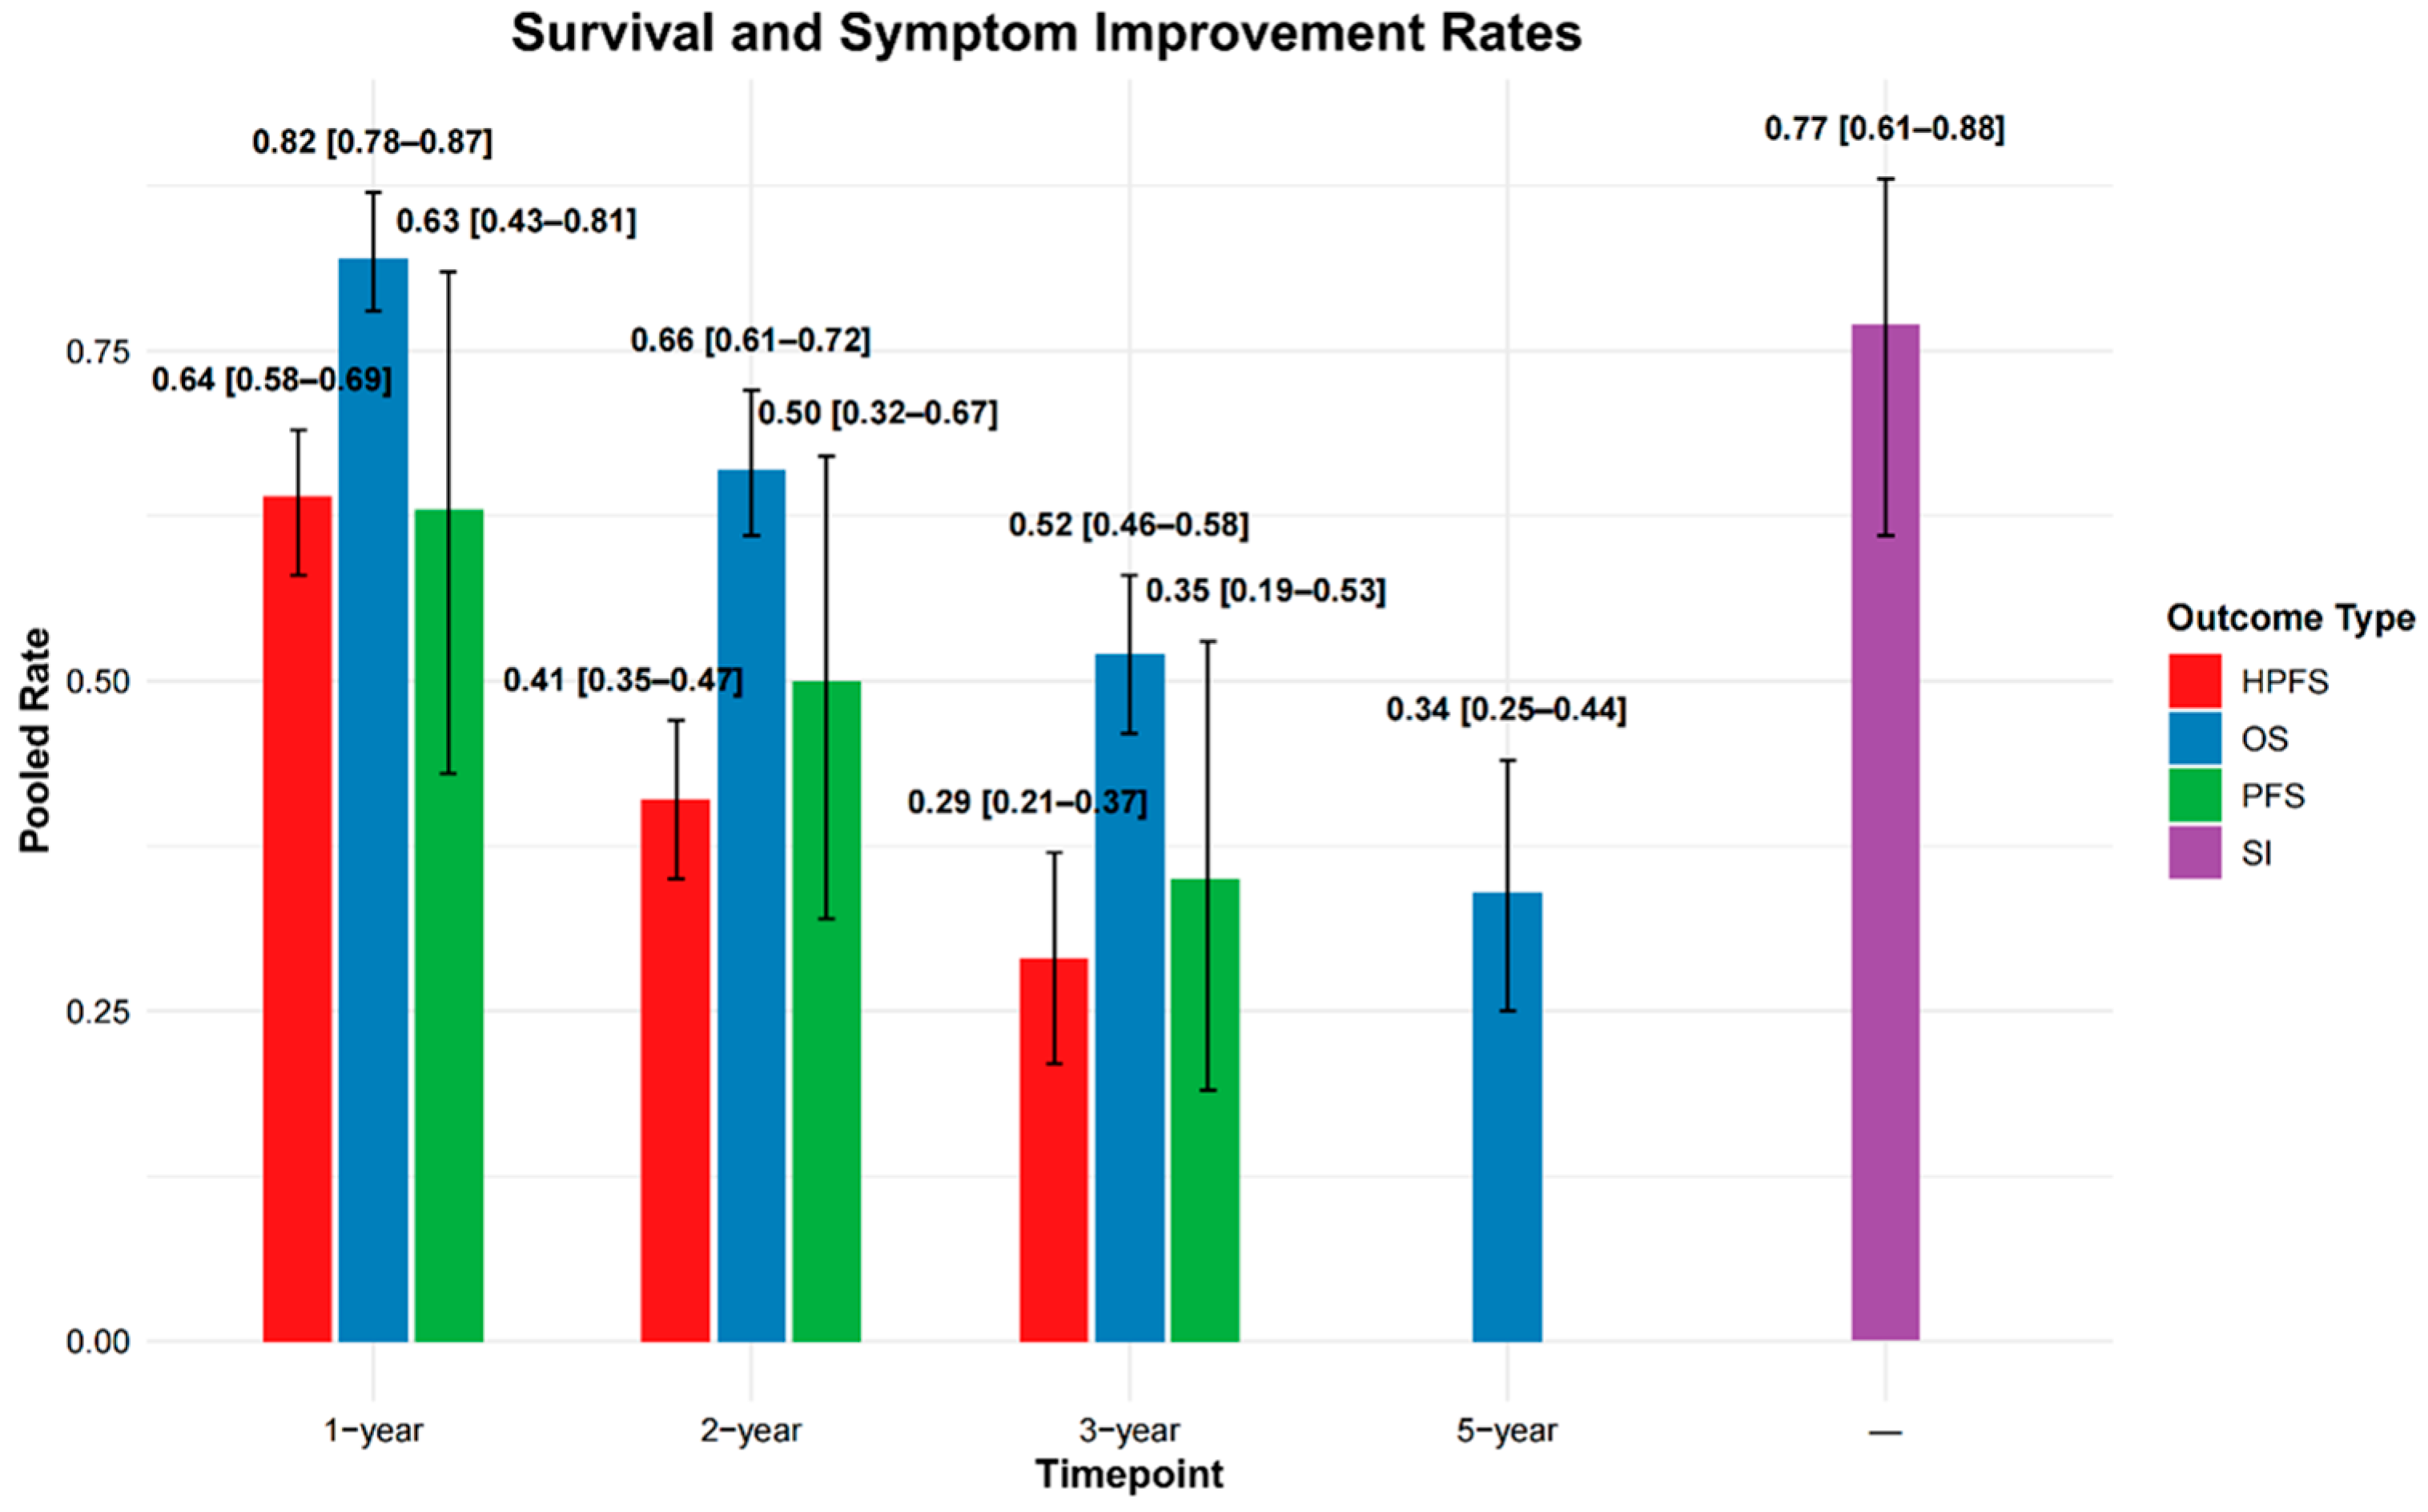

3.2.3. Survival Outcomes

3.2.6. Symptom Improvement